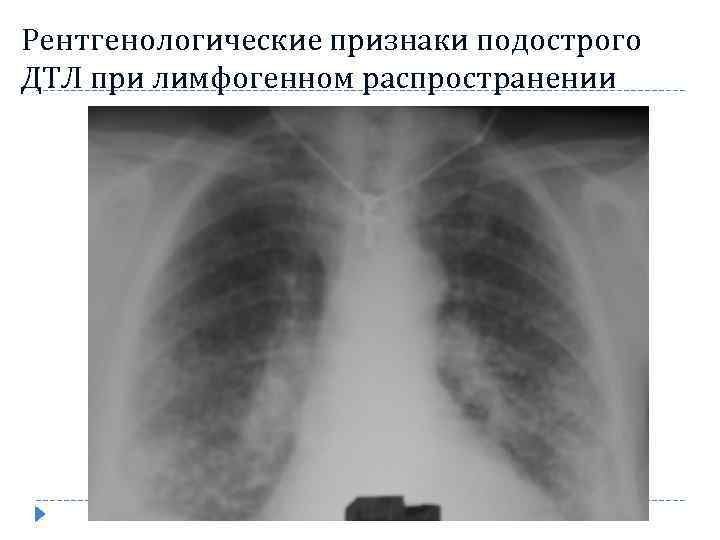

Рентгенологические признаки подострого ДТЛ при лимфогенном распространении Свойственны неравномерность поражения лёгких с чередованием измененных и неизмененных участков лёгочной ткани Асимметрия очагов Преимущественная локализация в средних прикорневых отделах Выраженные интерстициальные изменения обусловленные лимфангитом Возможность одностороннего поражения Более крупные очаги (5 -12 мм) по сравнению с гематогенным процессом

Рентгенологические признаки подострого ДТЛ при лимфогенном распространении Свойственны неравномерность поражения лёгких с чередованием измененных и неизмененных участков лёгочной ткани Асимметрия очагов Преимущественная локализация в средних прикорневых отделах Выраженные интерстициальные изменения обусловленные лимфангитом Возможность одностороннего поражения Более крупные очаги (5 -12 мм) по сравнению с гематогенным процессом

Рентгенологические признаки подострого ДТЛ при лимфогенном распространении 58

Рентгенологические признаки подострого ДТЛ при лимфогенном распространении 58